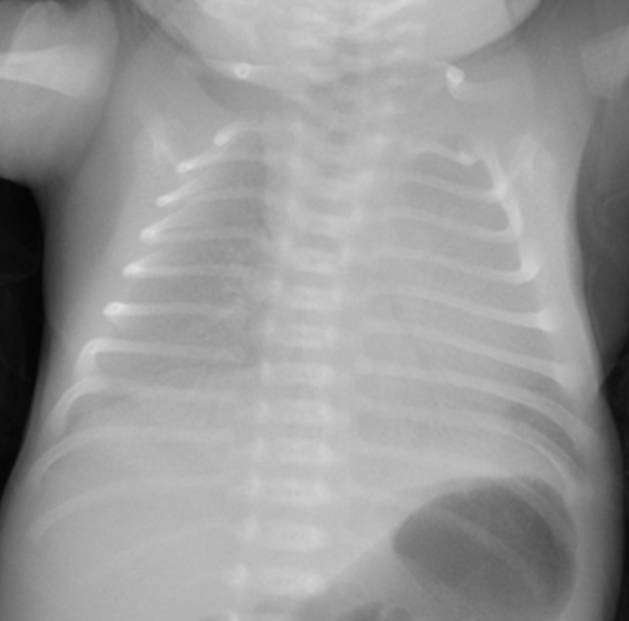

典型胸片結(jié)果:

(白肺表現(xiàn),IV級肺透明膜病變)

(II-III級肺透明膜病變)